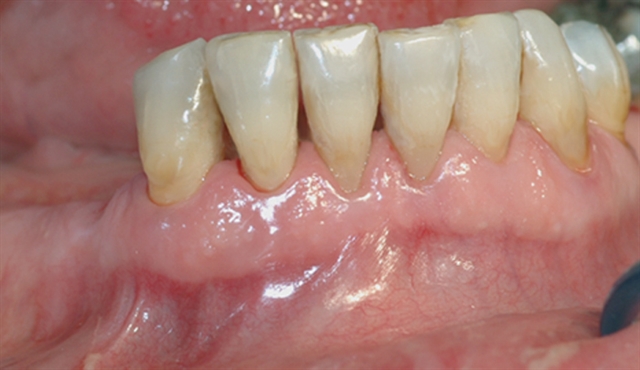

En undersøkelse med lommeregistrering avdekker likevel et omfattende bentap ved den ene tannen.

Instrumentet er her lagt utenfor tannkjøttet for å vise hvor stort festetapet egentlig er.